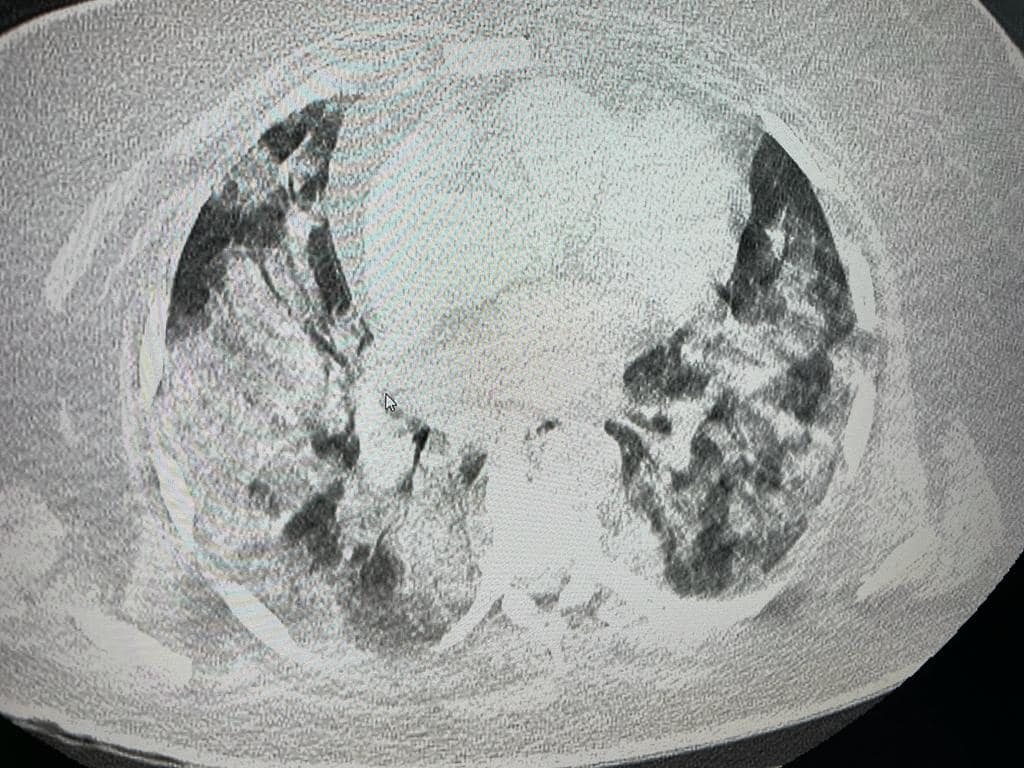

Autorităţile prezintă şi imagini din examenul CT pulmonar al unei paciente de 71 ani, nevaccinată pe motiv că are diabet.

„A stat acasă o săptămână și a venit în ultimul moment. A fost adusă cu saturație de 45, “corectată” până la 74 cu 15 l de O2. PO2 normal minim admis: 70.

95% afectare pulmonară și este nefumătoare”, au mai transmis autorităţile.